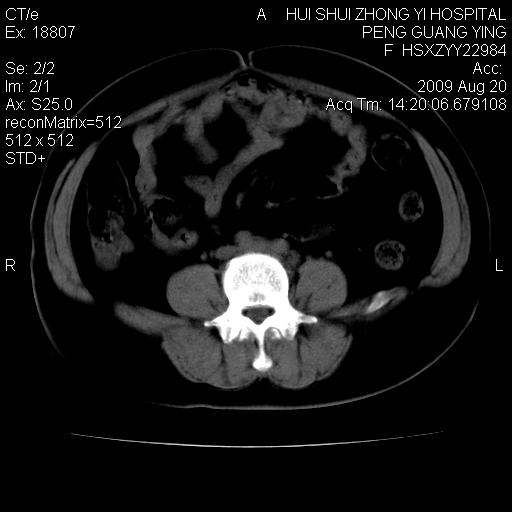

标题: CT21707:女,42岁,因发现下腹部包块2月。 [打印本页]

标题: CT21707:女,42岁,因发现下腹部包块2月。

病灶来源——子宫?附件?

从平扫角度看本人还是倾向于子宫肌瘤诊断,宫腔少量积液。

目前的影像表现显示肿块位于腹腔及盆腔,但具体定位,分清来源较困难,是否来源于卵巢、子宫无法定论,子宫直肠及子宫膀胱周围脂肪间隙尚较清晰,如果患者有过腹腔好或者盆腔手术史,也可以形成不典型的血中,最好手术后定为定性,我期待结果。

软组织密度,与子宫一致。双侧卵巢形态、密度好,不支持来源于卵巢。

病史不全面,病灶来源可能是子宫或卵巢,若临床有剖腹产、痛经史,则更支持前者,亦更支持子宫腺肌症